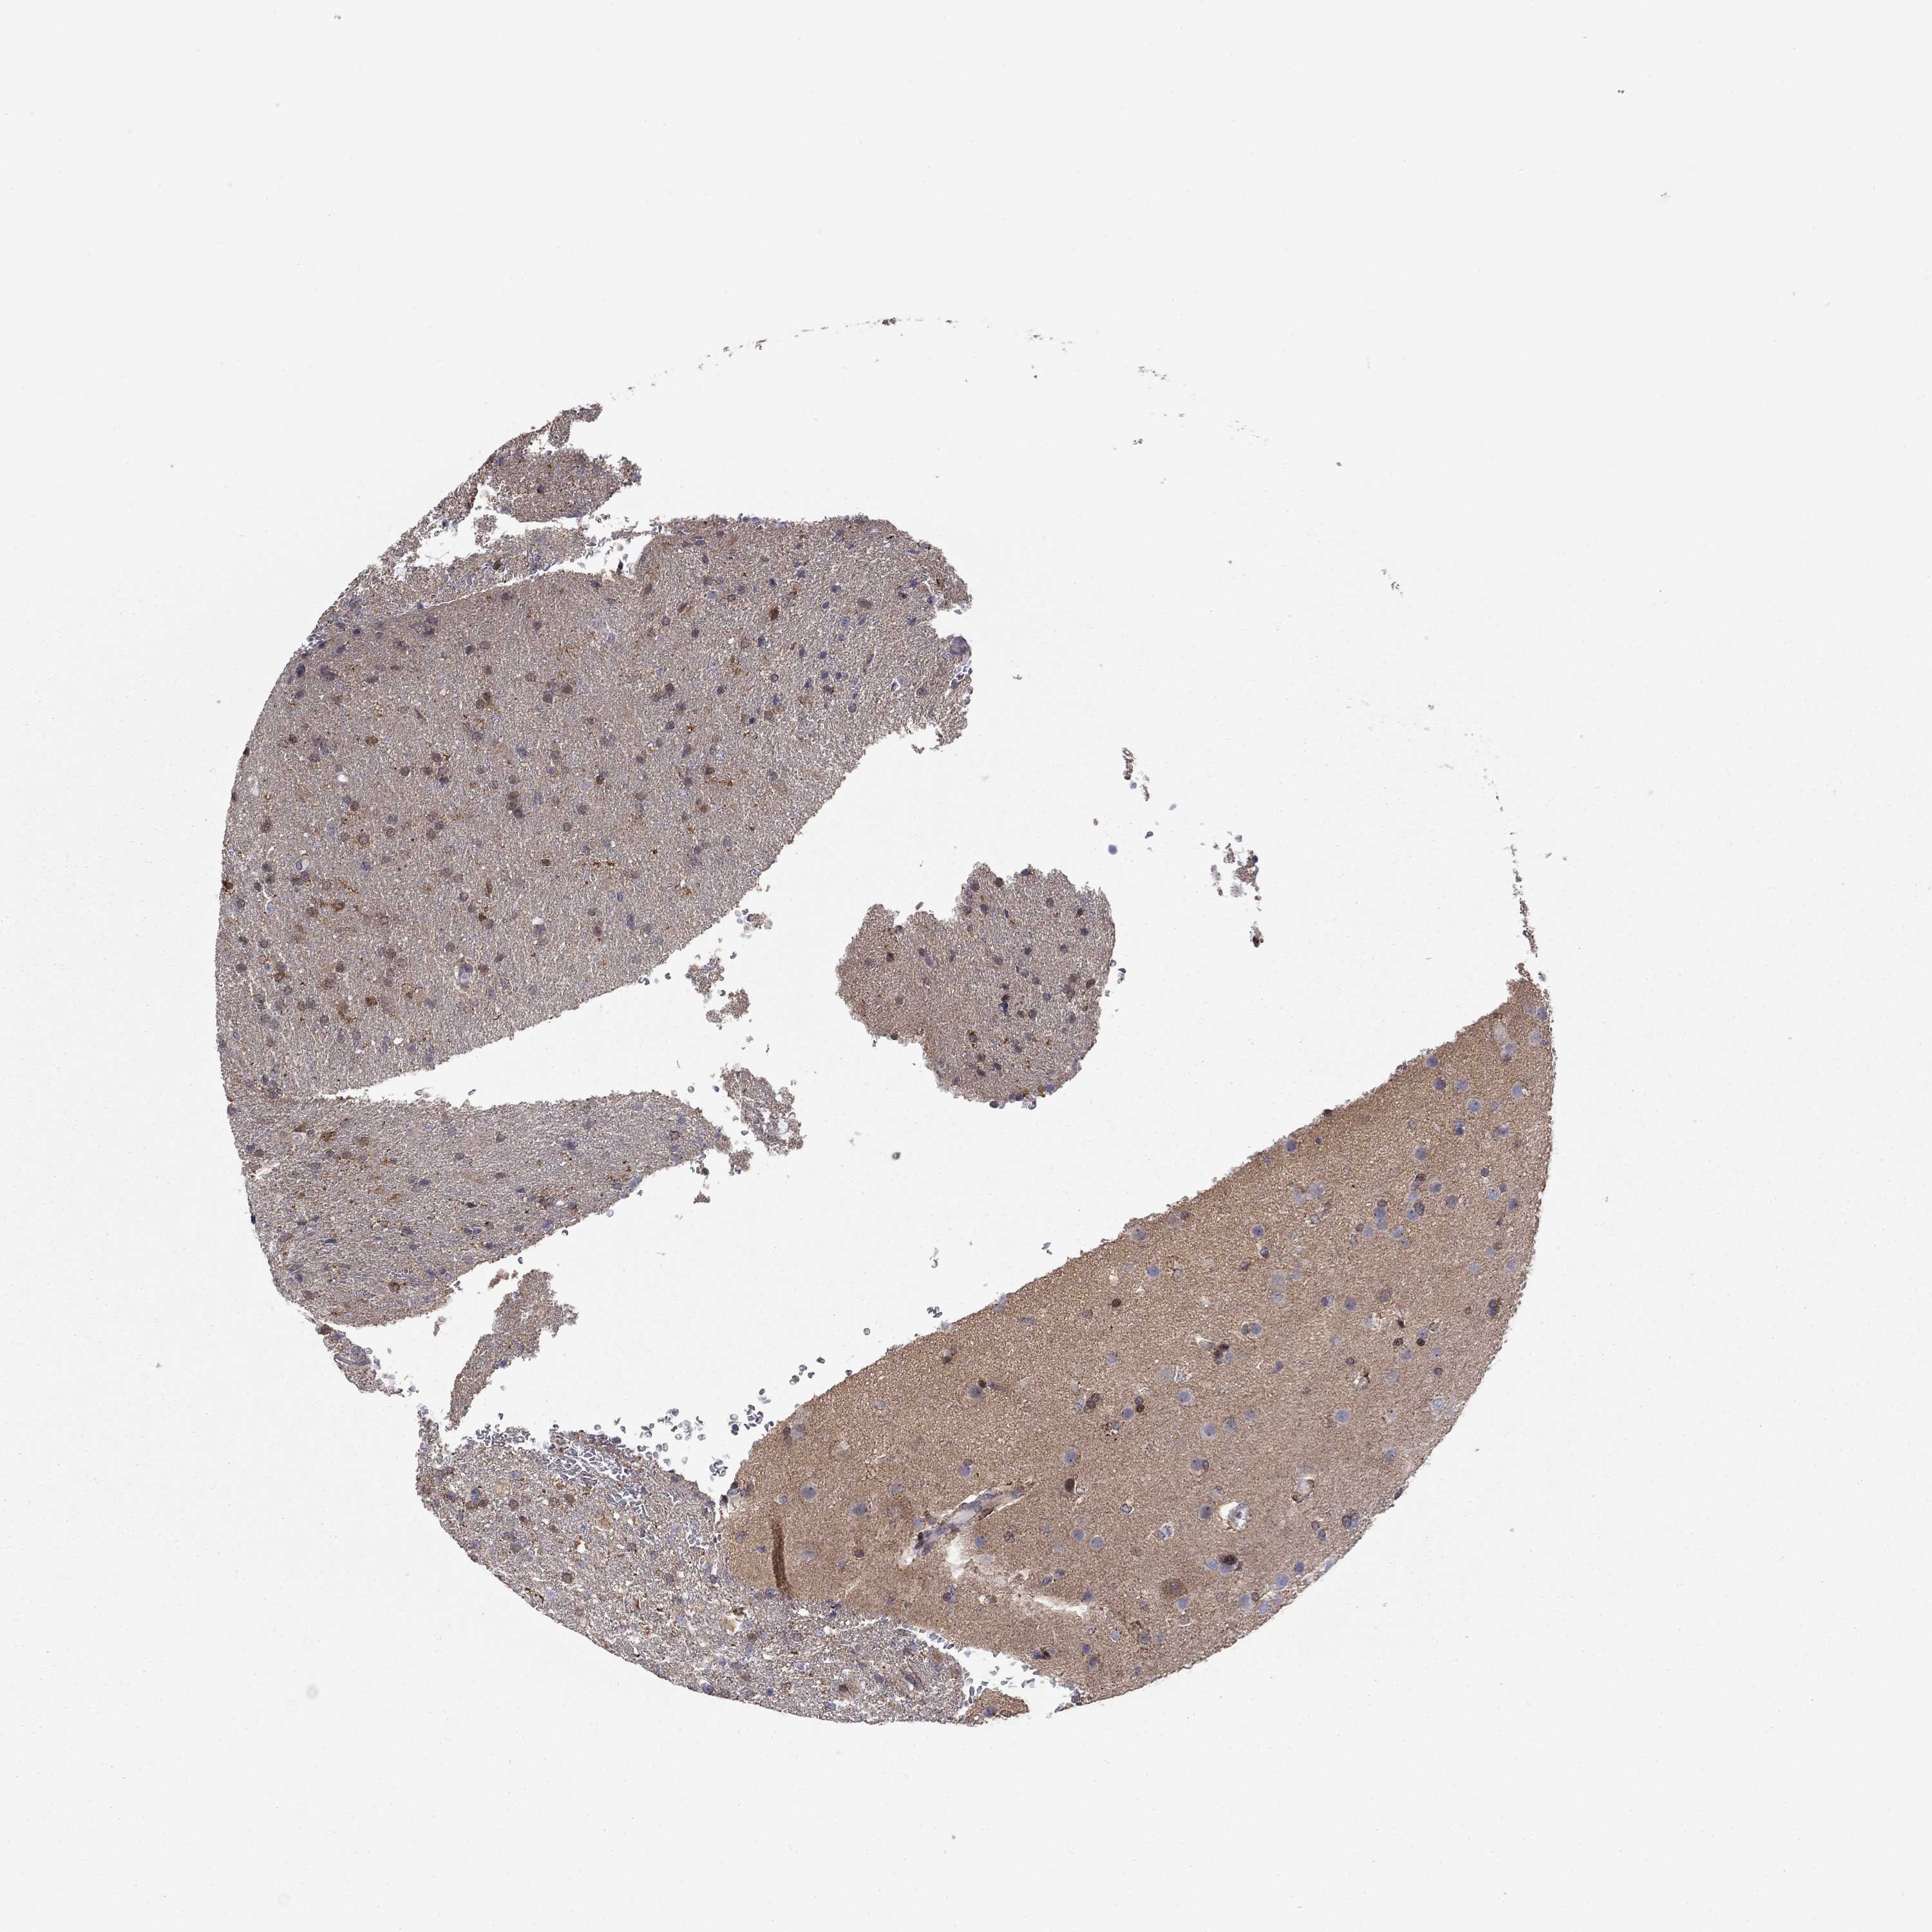

GLIOMA - Protein expressioni

A mouse-over function shows sample information and annotation data. Click on an image to view it in a full screen mode. Samples can be filtered based on level of antibody staining by selecting one or several of the following categories: high, medium, low and not detected. The assay and annotation is described here.

Note that samples used for immunohistochemistry by the Human Protein Atlas do not correspond to samples in the TCGA dataset.

Antibody stainingi

Antibody staining in the annotated cell types in the current human tissue is reported as not detected, low, medium, or high, based on conventional immunohistochemistry profiling in selected tissues. This score is based on the combination of the staining intensity and fraction of stained cells.

Each image is clickable and will lead to virtual microscopy that enables deeper exploration of all samples and also displays staining intensity scores, fraction scores and subcellular localization as well as patient and tissue information for each sample.

Antibody HPA073007

Staining

High

Medium

Low

Not detected

Intensity

Strong

Moderate

Weak

Negative

Quantity

>75%

75%-25%

<25%

None

Location

Nuclear

Cytoplasmic/membranous

Cytoplasmic/membranous,nuclear

Glioma, malignant, Low grade

Glioma, malignant, High grade

Glioma, malignant, NOS